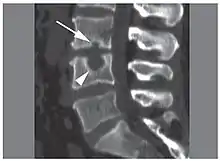

| X-ray image of Schmorl's nodes in the lumbar spine | |

Schmorl's nodes can be detected with X-rays, although they can be imaged better by CT or MRI. They are considered to be vertical disc herniations through the cartilaginous vertebral body endplates. Schmorl's nodes can sometimes be seen radiographically, however they are more often seen on MRI, even when not visible on plain X-rays. They may or may not be symptomatic, and their etiological significance for back pain is controversial. In a study in Spine by Hamanishi, et al., Schmorl's nodes were observed on MRI in 19% of 400 patients with back pain, and in only 9% of an asymptomatic control group. The authors concluded that Schmorl's nodes are areas of "vertical disc herniation" through areas of weakness in the endplate.[5]